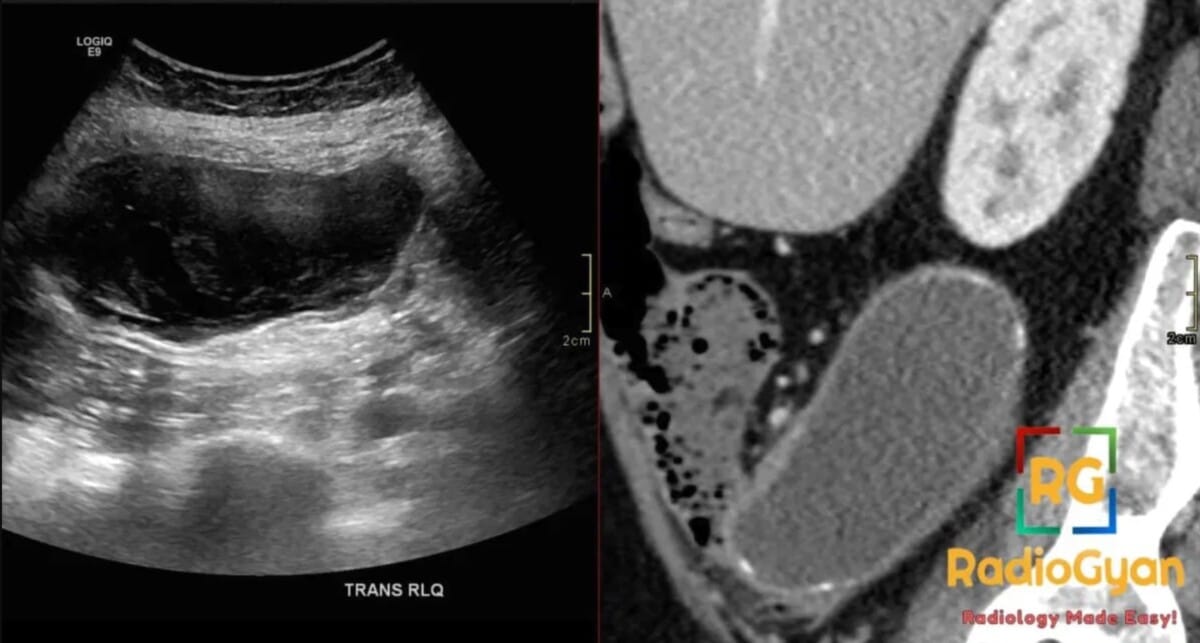

62 yr female presenting with a palpable right lower quadrant mass and chronic abdominal pain.

Diagnosis: Appendiceal Mucocele

- The “Onion-skin sign” on ultrasound is considered pathognomonic, representing multiple echogenic layers of inspissated mucin.

- US: Elongated tubular mass in the right lower quadrant; characteristic “onion-skin” texture with internal echogenic layers; “drumstick” or “pear-shaped” appearance; no internal blood flow on Doppler; mucinous ascites from rupture appears as low-level echoes with ill-defined septations.

- Signs: Onion-Skin Sign: Pathognomonic ultrasound finding of multiple echogenic layers; Whorly/Onion Peel Appearance: CT description of layered mucin within the dilated lumen.